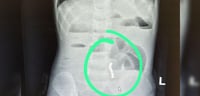

במלר"ד הילדים התקבל הפעוט על ידי ד"ר אהוד רוזנבלום, מנהל המלר"ד, ומיד בוצע לו צילום חזה בו זוהתה סוללת דיסק התקועה בוושט - ממצא המחייב טיפול דחוף.

בעקבות הממצאים הוזעק ד"ר אייל זיפמן, מנהל שירות גסטרואנטרולוגיה ילדים במרכז רפואי מאיר, והוחלט להכניס את הילד במהירות לחדר ניתוח. "הסוללה נמצאה נעוצה בוושט ונשלפה בשלמותה באמצעות גסטרוסקופיה, פעולה אנדוסקופית שבה מכניסים מצלמה דרך הפה לדרכי העיכול העליונות. מסביר ד"ר זיפמן.